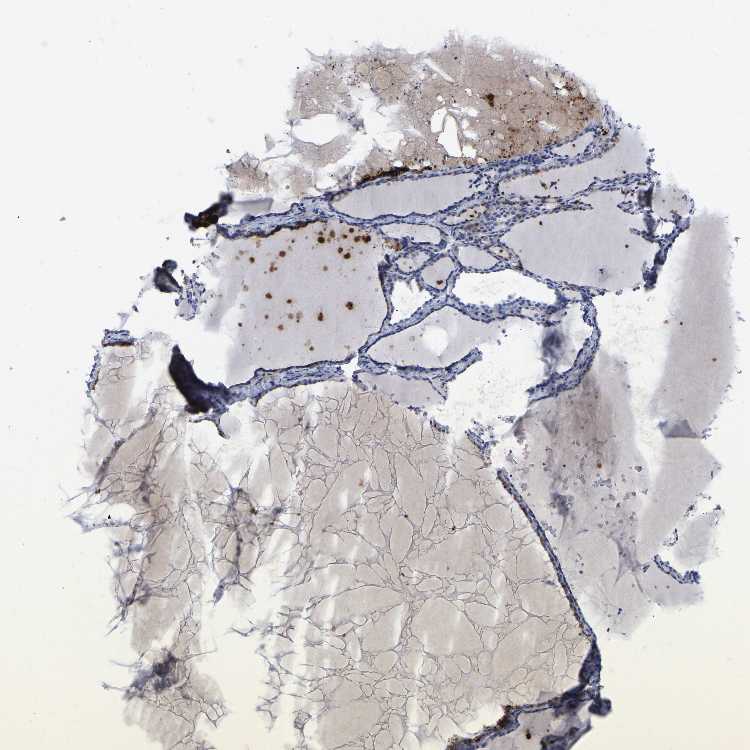

THYROID GLAND - Antibody stainingi

Antibody staining in the annotated cell types in the current human tissue is reported as not detected, low, medium, or high, based on conventional immunohistochemistry profiling in selected tissues. This score is based on the combination of the staining intensity and fraction of stained cells.

Each image is clickable and will lead to virtual microscopy that enables deeper exploration of all samples and also displays staining intensity scores, fraction scores and subcellular localization as well as patient and tissue information for each sample.

Antibody HPA018468

Glandular cells Not detected